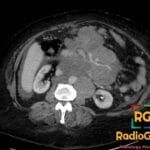

Diagnosis: Appendiceal Mucocele

- CT: Round or tubular low-attenuation (17-26 HU) cystic mass near water density; well-encapsulated; wall calcification is a strong diagnostic feature; wall irregularity and mural nodularity suggest malignancy (cystadenocarcinoma).

- Signs: Onion-Skin Sign: Pathognomonic ultrasound finding of multiple echogenic layers; Whorly/Onion Peel Appearance: CT description of layered mucin within the dilated lumen.

- Wall calcification on CT is highly specific for the diagnosis, though present in less than 50% of cases.

- DDx: Hydrosalpinx (lacks onion-skin sign); Tubo-ovarian abscess (fever, complex appearance); Acute appendicitis (diameter <15 mm, inflammatory clinical picture); Ovarian pathology (distinct anatomical origin on MRI).